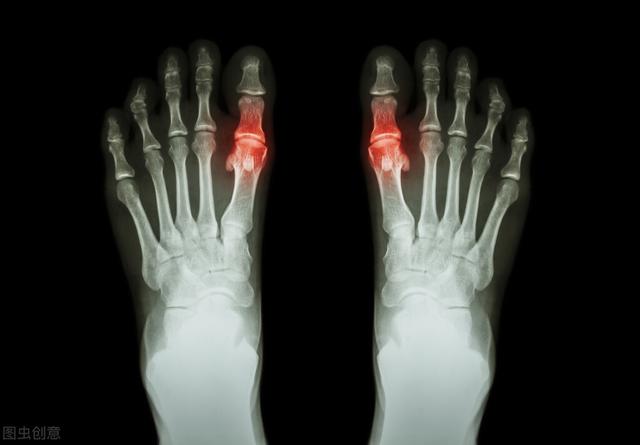

La détermination de la goutte dépend principalement des articulations. Au début de l'apparition de la goutte, 53 % à 70 % des patients ont les articulations du premier orteil (appelées goutte du pied) rouges, gonflées, chaudes et douloureuses, généralement multiples, certaines pouvant aussi se manifester sous forme d'articulations multiples. Elle est fixe et asymétrique, et peut progressivement envahir des articulations plus importantes telles que les chevilles, les genoux, les poignets et les coudes.

Les symptômes typiques de la goutte sont des douleurs rouges, enflées et chaudes dans les articulations. L'articulation la plus fréquemment touchée est le gros orteil (terme médical : premier métatarsien), tandis que d'autres sont fréquentes dans les articulations de la cheville, du genou et du coude. Les symptômes apparaissent souvent soudainement la nuit. L'examen hospitalier consiste principalement à vérifier le taux d'acide urique dans le sang. Toutefois, il convient de noter que certains patients n'ont pas un taux d'acide urique élevé lorsqu'ils font une crise de goutte. Il est donc recommandé de se rendre à l'hôpital pour un examen et un traitement standardisé. Les cliniques ambulatoires voient souvent l'abus d'analgésiques conduire à l'insuffisance rénale, ce qui est très regrettable. En outre, tous les patients ayant un taux d'acide urique élevé ne développeront pas la goutte, mais ils présenteront également d'autres risques, de sorte qu'un taux d'acide urique élevé devra, dans une certaine mesure, être contrôlé à l'aide de médicaments (voir l'article à la une que j'ai posté).

Lors d'une crise aiguë de goutte, on observe souvent une rougeur, un gonflement, une chaleur, une douleur et un dysfonctionnement localisés importants dans les articulations touchées (le plus souvent le gros orteil et le dos du pied).